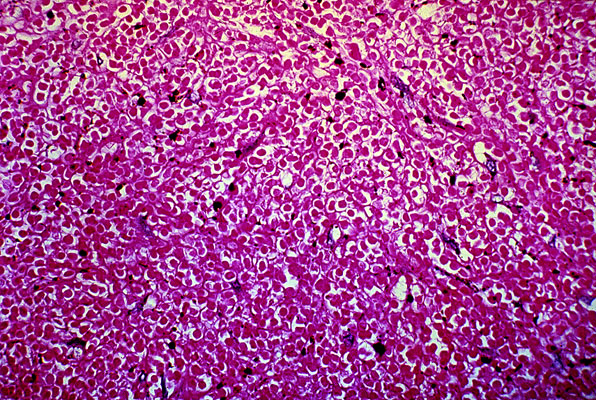

Recent thrombus, femoral vein, photomicrograph, H/E, x100

In a recently formed

thrombus

, all one sees microscopically is a network of

fibrin

strands with trapped RBCs, and the normal ratio of WBCs.